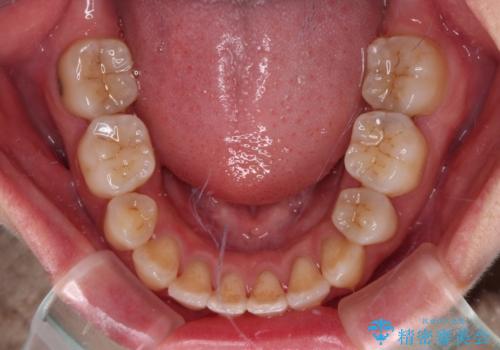

Eラインを改善したい ハーフリンガルによる抜歯矯正

- 口元の突出感を気にして来院された患者様です。

上下左右の第一小臼歯4本を抜歯して口元を下げる治療計画としました。

舌の突出癖が強く、口元を引っ込める力に拮抗してしまい、抜歯スペースを閉じるまでに時間がかかりました。

また途中出産もありましたが、無事に治療を終えることができました。